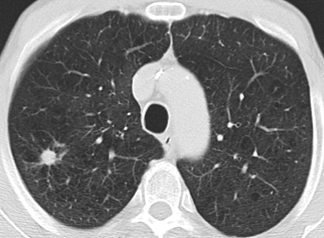

Beispielhafte Aufnahmen verschiedener Erkrankungen

(Lungenklinik Lostau)

Die High-Resolution-Computertomographie (HRCT) ist eine spezielle CT-Technik mit sehr hoher Detailauflösung. Sie ist besonders wichtig für die Diagnostik und Verlaufskontrolle interstitieller Lungenerkrankungen (ILD), da feine Muster im Lungengewebe differenziert beurteilbar werden.

Interstitielle Lungenerkrankungen (ILD) sind Erkrankungen, bei denen sich das Lungengewebe durch Entzündung oder Vernarbung verändert. Die High-Resolution-Computertomographie (HRCT) ist dabei ein zentrales Werkzeug, weil typische Muster in der Bildgebung wichtige Hinweise auf Ursache und Stadium geben.